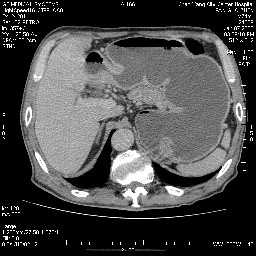

女,74岁,呕吐10余日

十二指肠水平段腔内占位伴梗阻,中等度较为均匀的强化,洗脱慢,区域淋巴结显示增多,符合腺癌表现。下腔静脉变异。

感谢诸位的指教,补充病史:该患胃镜结果提示十二指肠降曲外压性狭窄。请大家帮助分析下原发部位

病变主要位于钩突(癌)。如是壶腹部,肝内外胆管扩张明显。

病变考虑为钩突癌。

十二指肠降段扩张,水平段狭窄成鼠尾状,肠壁明显增厚,胰腺勾突增大成不均匀强化,其内可见低密度区,胆囊增大,1十二指肠水平段腺癌侵犯胰腺勾突可能大,2胰腺癌侵犯十二指肠(只有胆囊增大没有肝内外胆管扩张不好解释)代除外.

十二指肠降段扩张,水平段狭窄成鼠尾状,肠壁明显增厚,胰腺勾突增大成不均匀强化,其内可见低密度区,胆囊增大,1十二指肠水平段腺癌侵犯胰腺勾突可能大,2胰腺癌侵犯十二指肠 。

今日手术结果:胰腺钩突癌侵犯十二直肠,腹腔淋巴结转移.